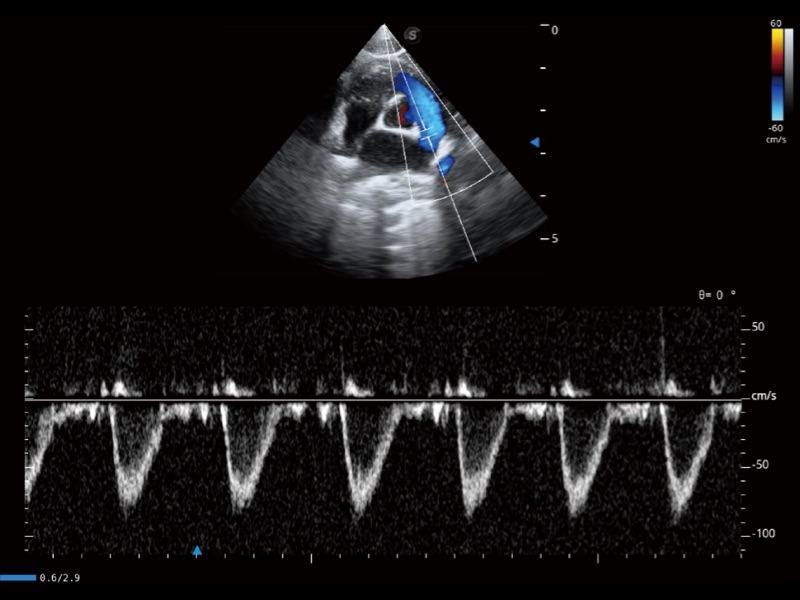

能夠基于左心室壁追蹤和辛普森法,自動計(jì)算射血分?jǐn)?shù),支持多個可移動點(diǎn)描跡,與手動測量相比,極大節(jié)省了動物醫(yī)生的時(shí)間和精力。